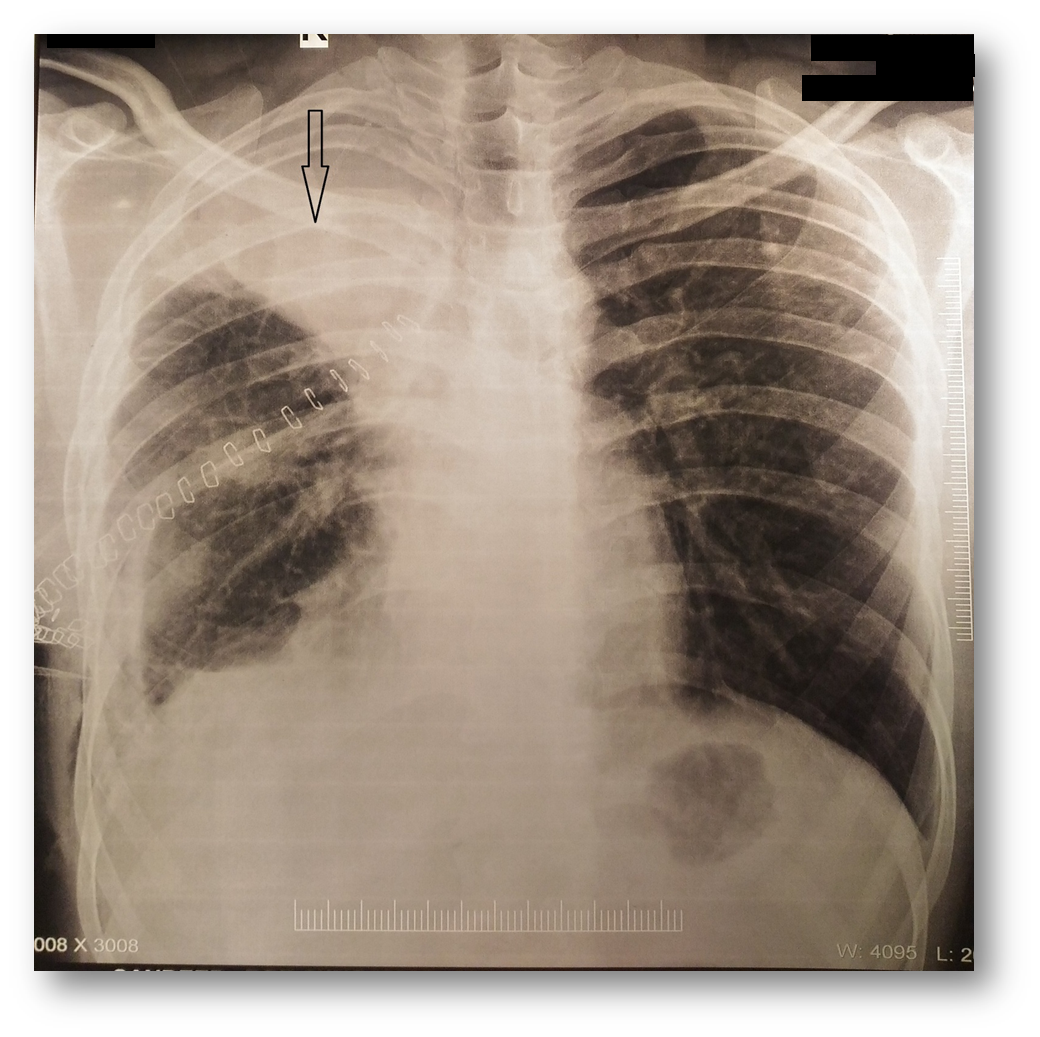

A 21-year-old man in otherwise good health underwent a right upper lobectomy for aspergilloma. The surgery was uneventful. On the third postoperative day, he developed a fever and dull aching pain in his right chest. Plain x-ray revealed an opacity in the right upper zone (Figure 1). Contrast enhanced computed tomography (CT) scan revealed intracavity mass with air bubbles and a long radio-opaque marker, reported by the radiologist as a retained surgical sponge (gossypiboma) (Figure 2).